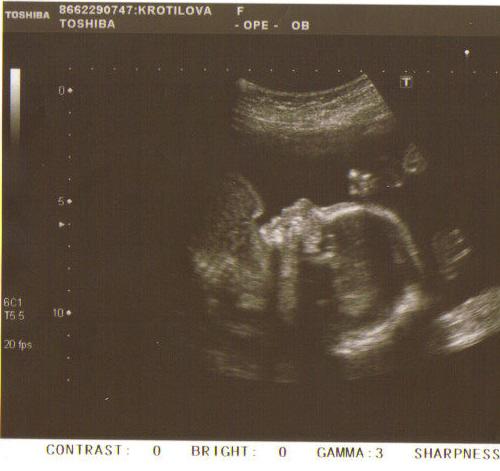

27.01.2010 Mě maminka poprvé viděla na UTZ, vypadalo jsem jako bublinka...

17.03.2010 Taťka mě poprvé viděl na UTZ :o) měřilo jsem krásných 7cm a ukázalo jsem jim, jak se už pěkně umím vrtět...

17.05.2010 Další UTZ, ukázala jsem jim své "kávové zrnko" :o) a byli moooc šťastný!!! A teď mi konečně už snad vymyslej jméno!